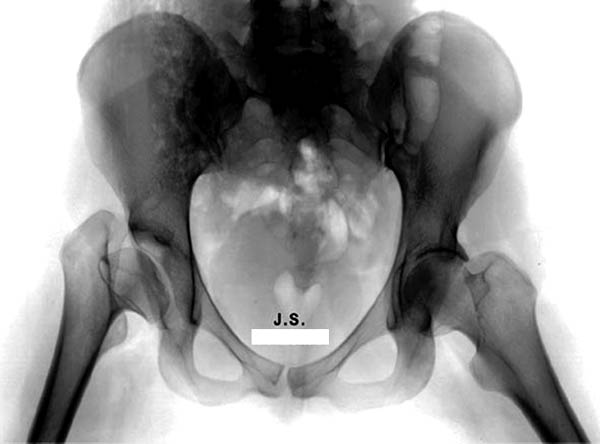

Здесь комбинированная патология тазобедреннего сустава, связанная с высокостоящим вертелом и отсутствием (ротирована?) шейкой. А на стороне вертлужной впадины диспластический сустав. Обычно высоко расположенный вертел приводит к уменьшению силы мышц абдукторов, но отстутствие шейки привело к вертикальному расположению  сил в суставе. Боли появляются из-за вертикального давления, а неровные контуры головки приводят к ограничению движений в суставе. Такое состояние быстро изнашивает сустав, и больные в молодом возрасте заканчивают тотальным протезированием.

Представленный случай имеет схожесть....,  и последний снимок после 2 х лет.